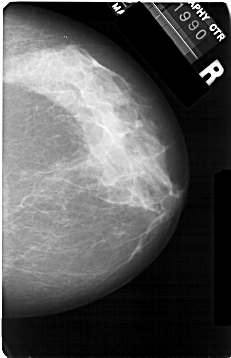

A_1301_1.RIGHT_CC

RIGHT_CC LINES 5356 PIXELS_PER_LINE 3451 BITS_PER_PIXEL 12 RESOLUTION 43.5 NON_OVERLAY